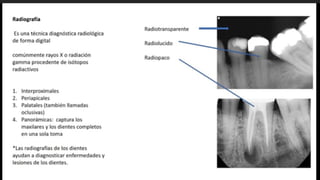

DIGITAL